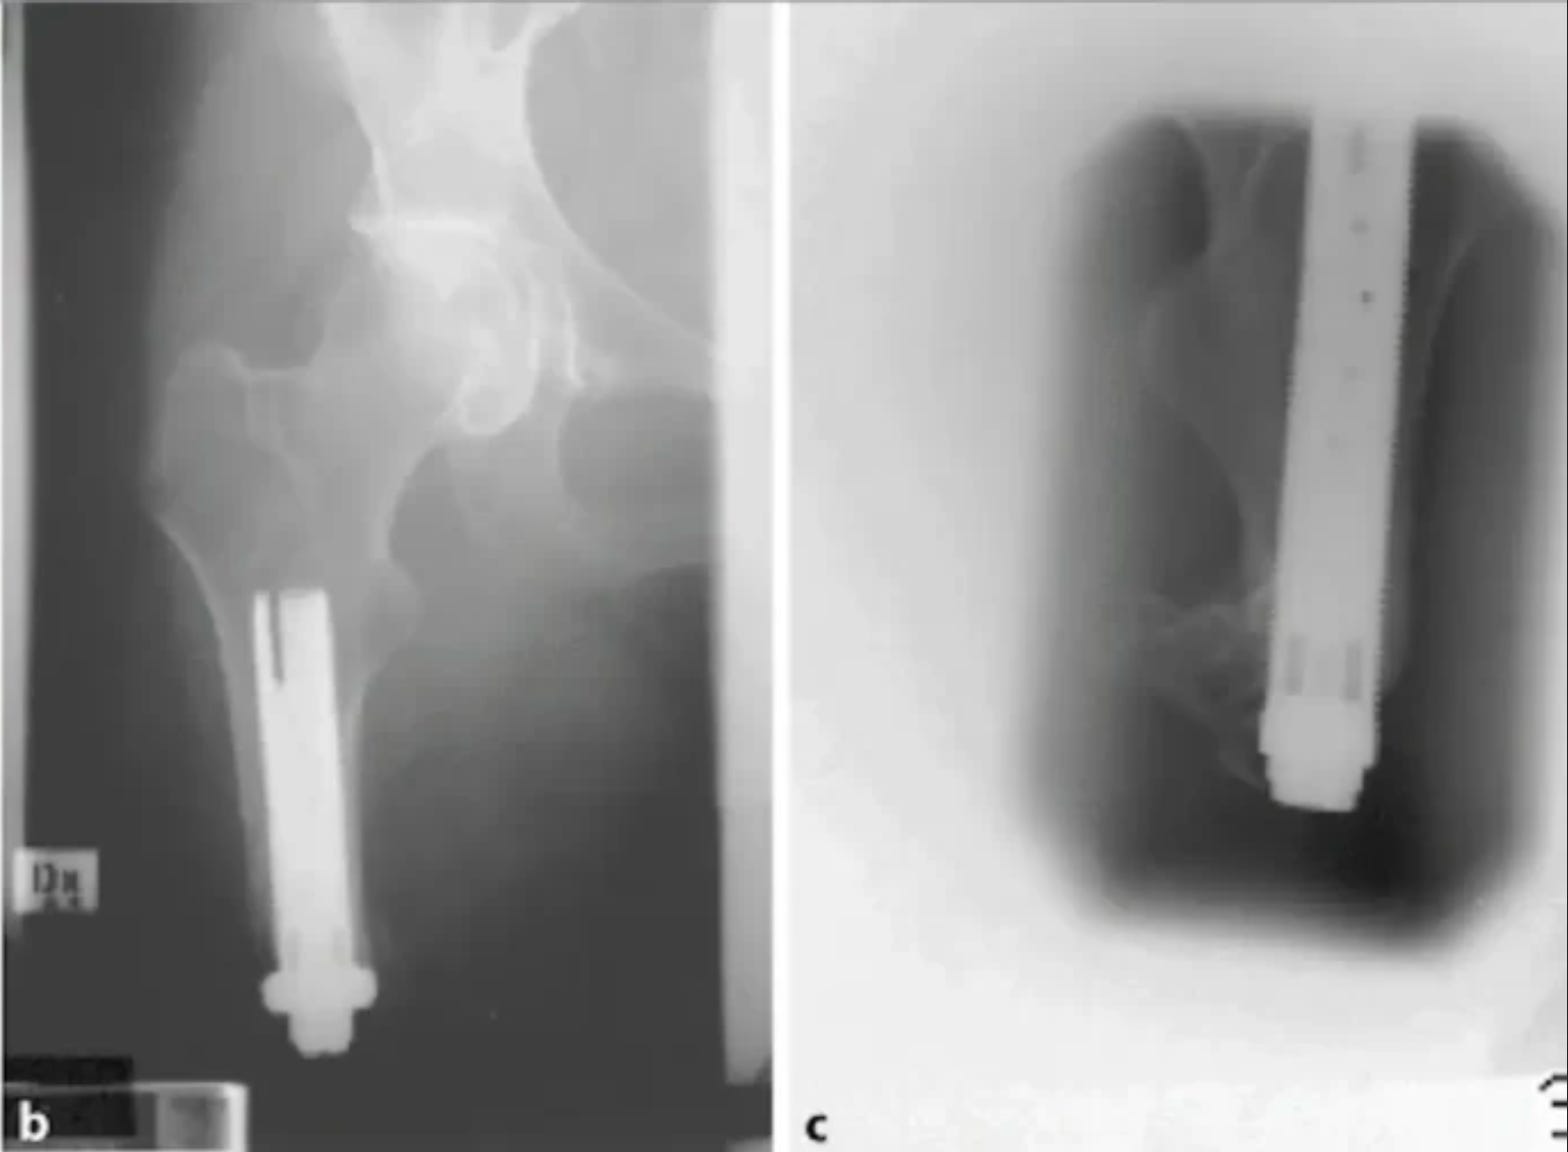

As I’ve written before, I hope to undergo a procedure called osseointegration that allows a direct connection between the bone and the prosthesis. Since my surgeon told me that Medicare may not pay for the implant, I’m also looking at more conventional prostheses.

The next step is inserting the “sleeve” that will eventually hold the post at the top of the prosthesis.

They could do the implantation surgery as soon as the end of this month, though when I take into account what Medicare will cover, that’s too soon.

My 60 days without hospital or SNF care in this Benefit Period ends on 15 January. The implant surgery is scheduled for 22 January, and my new Benefit Period will begin when I check into the hospital on the 21st.